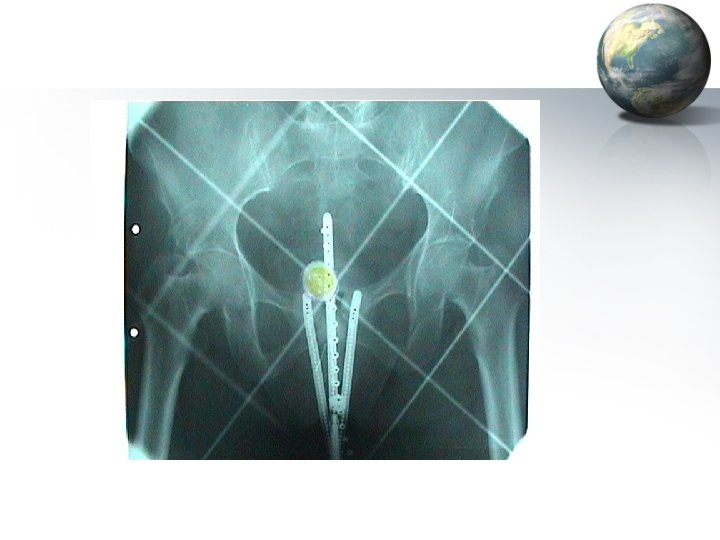

Surgery for Carcinoma cervix • Stage Ia 2 IIa disease – Wertheim’s / Meig’s hysterectomy (Extended hysterectomy with pelvic lymphadenectomy) • • • Uterus including cervix Adnexae (Ovaries spared in the young) Wide resection of the parametrium Removal of vaginal cuff Dissection of peri-ureteral tissues Pelvic lymphadenectomy • Stage IV a disease – Exenteration